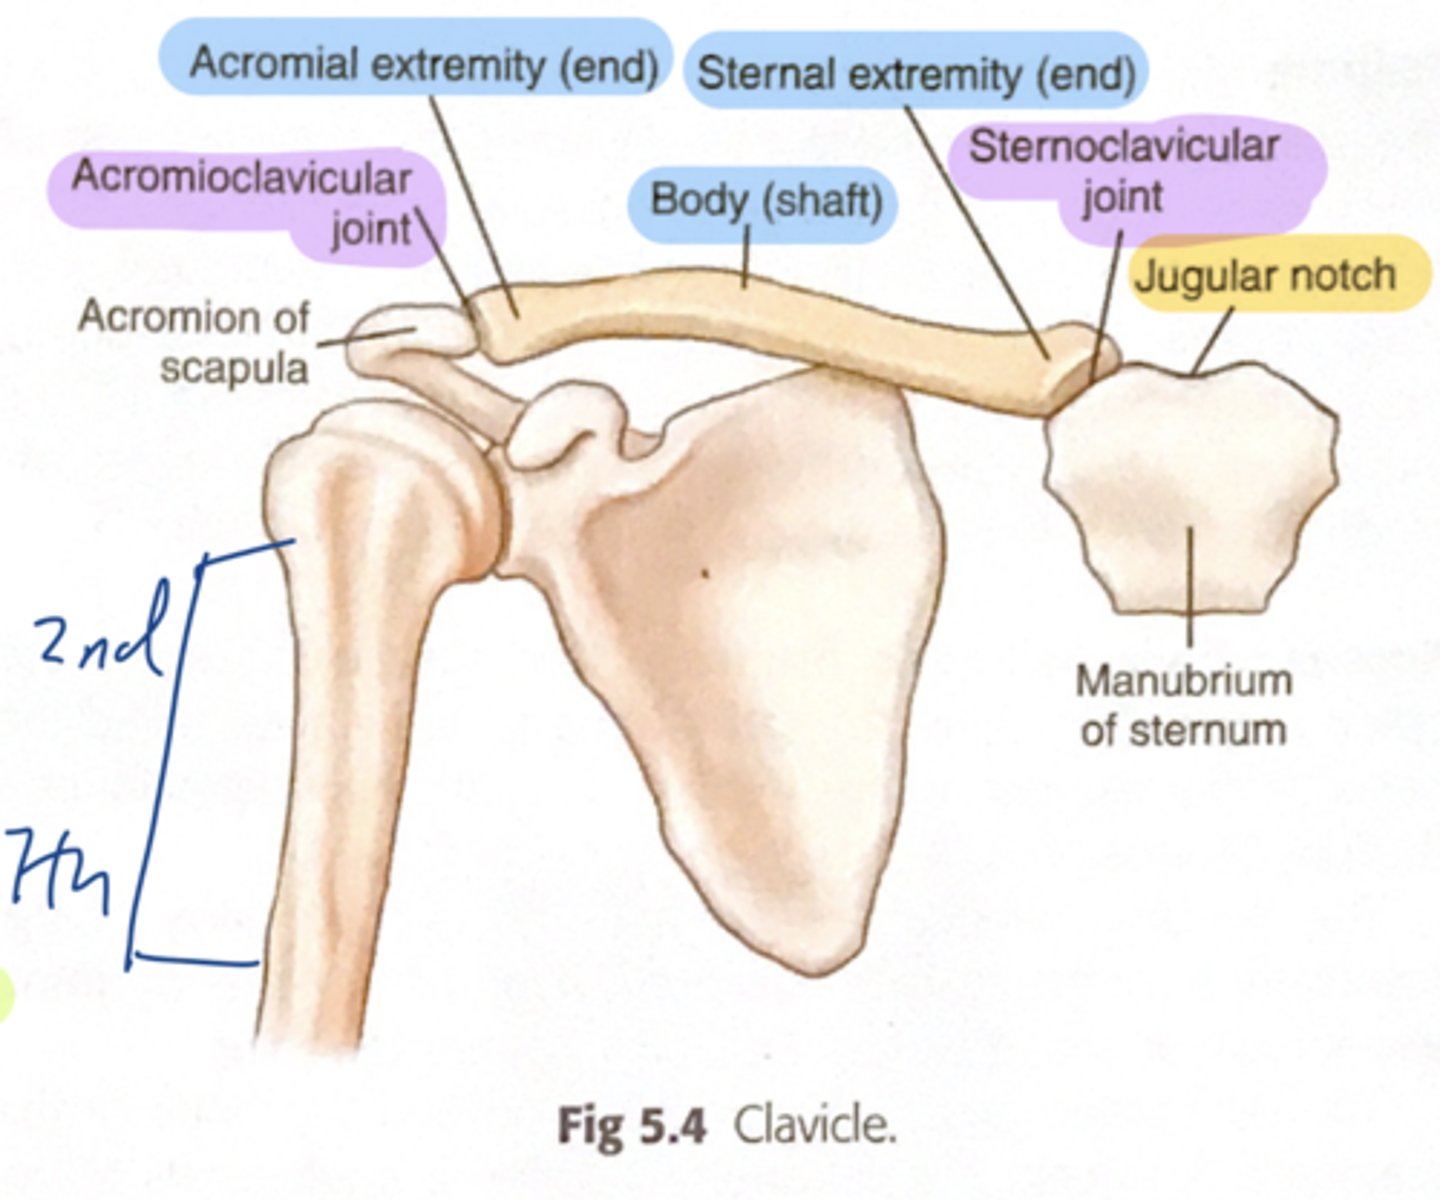

The clavicle connects the _____ to the ____

connect UE to trunk

The clavicle suspends____________________

the scapula and free limb from the trunk

The clavicle forms________________________

one of the boundaries of the cervico-axillary canal together with the scapula and 1st rib

What is the cervico-axillary canal?

passage between neck and arm

What does the cervico-axillary canal do?

protects the neurovascular bundle supplying the arm

The clavicle transmits___________

shocks from the UE to the axial skeleton

Sternal end of the shaft of the clavicle articulates:

articulates with manubrium via the sternoclavicular joint

Acromial end of the shaft of the clavicle articulates:

articulates with acromion via acromioclavicular joint

Clinical relevance: fracture of the clavicle

Inflection point: The junction between the medial 2/3rd and lateral 1/3rd. The inflection point is the weakest point of the clavicle, more prone to fractures. The medial 2/3rd is going to be displaced superiorly by the action of the SCM (sternocleidomastoid) muscle